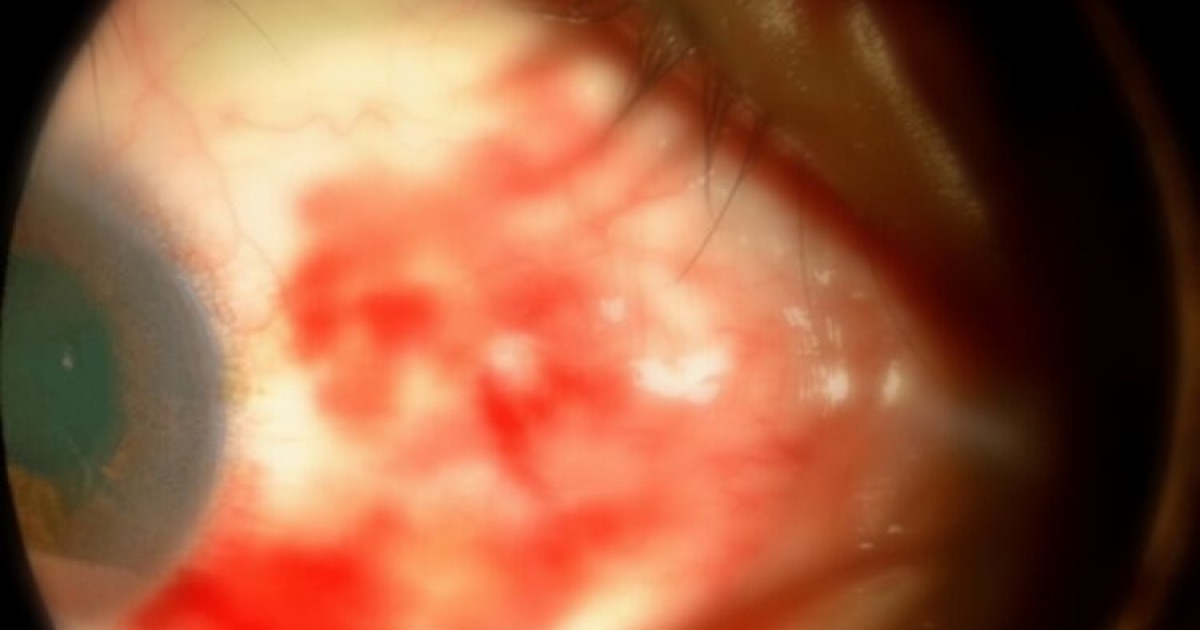

The cases included a 9-year-old boy, several teenagers, and adults up to age 62. Four injuries were directly caused by a shuttlecock impact, two stemmed from broken glasses shattering during play, and one resulted from a racket strike. While most patients initially had good vision, two already exhibited significant visual acuity loss upon presentation. The most severe cases involved corneal sclera lacerations (tears in the eye’s outer layer) and hyphema (bleeding within the eye), leading to potentially permanent vision impairment.

Perhaps the most harrowing case involved a 16-year-old male whose vision was critically compromised when fragments of broken glasses penetrated his eyeball. Despite emergency surgery, doctors expressed a grim prognosis. This case underscores the vulnerability of players who don’t wear appropriate eye protection, and the dangers of playing with standard, non-sports-rated eyewear.